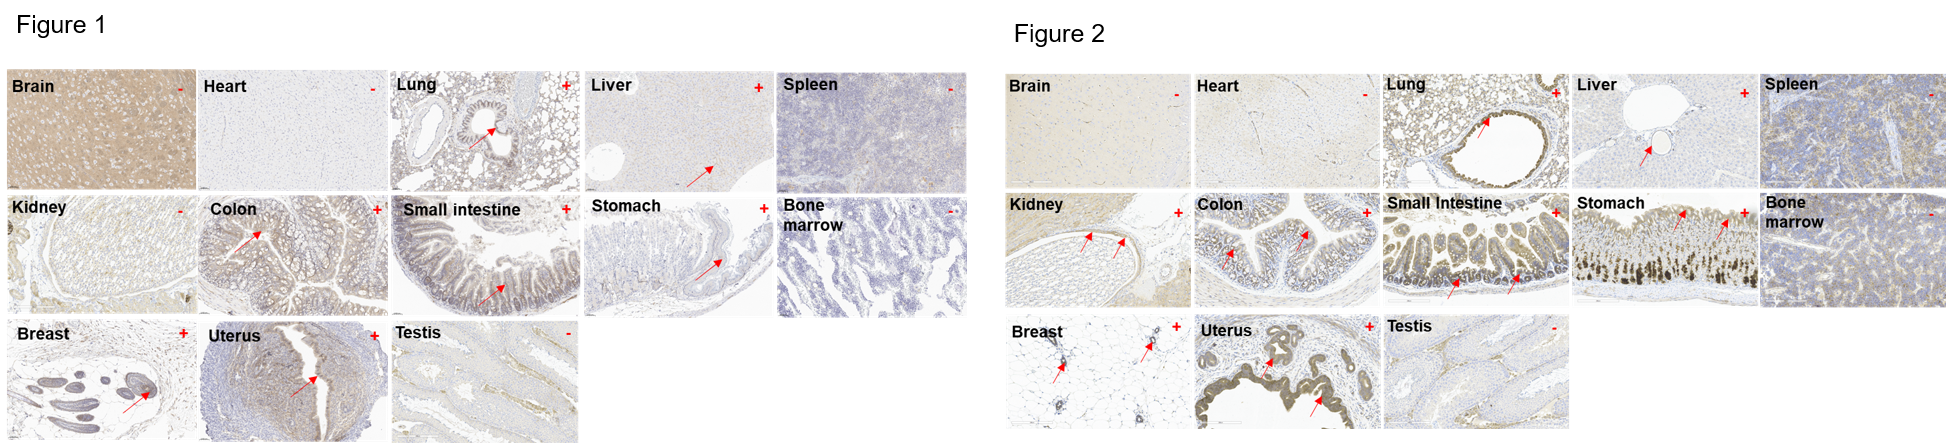

- Mouse HER2 was detected in the lung, liver, stomach, colon, small intestine, uterus and breast of wild-type mice.

IHC analysis of HER2 expression

Immunohistochemical (IHC) analysis of HER2 protein expression in wild-type mice and B-NDG hHER2 mice. Thirteen major tissues were collected from wild-type mice and homozygous B-NDG hHER2 mice and analyzed by IHC with anti-mouse HER2 antibodies (ab214275) and anti-human HER2 antibodies (ab16662). Mouse HER2 was detected in the lung, liver, stomach, colon, small intestine, uterus and breast of wild-type mice (Figure 1). Human HER2 was detected in the lung, liver, stomach, colon, small intestine, uterus, breast and kidney of homozygous B-NDG hHER2 mice (Figure 2).